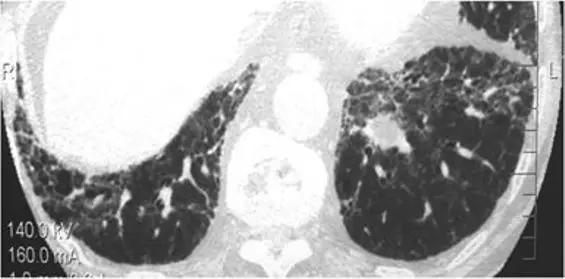

石棉肺也以网状模式为主,因此可能模仿IPF。其特征是在早期存在胸膜下网状结构和胸膜下点状混浊。可能存在磨玻璃影的区域,且发现主要在后段和基底段。在后期,蜂窝样改变是很常见的发现。与IPF鉴别诊断的线索可能是存在胸膜斑、弥漫性胸膜增厚、胸膜下曲线或实质带。

*石棉肺。 HRCT下叶水平扫描显示“网状模式”,其特征是存在胸膜下牵引支气管扩张和支气管扩张,支气管周围血管间质和小叶间隔的蜂窝状和增厚。钙化的胸膜和胸膜斑(白色和黑色箭头)的存在为诊断石棉肺提供了明确的线索。